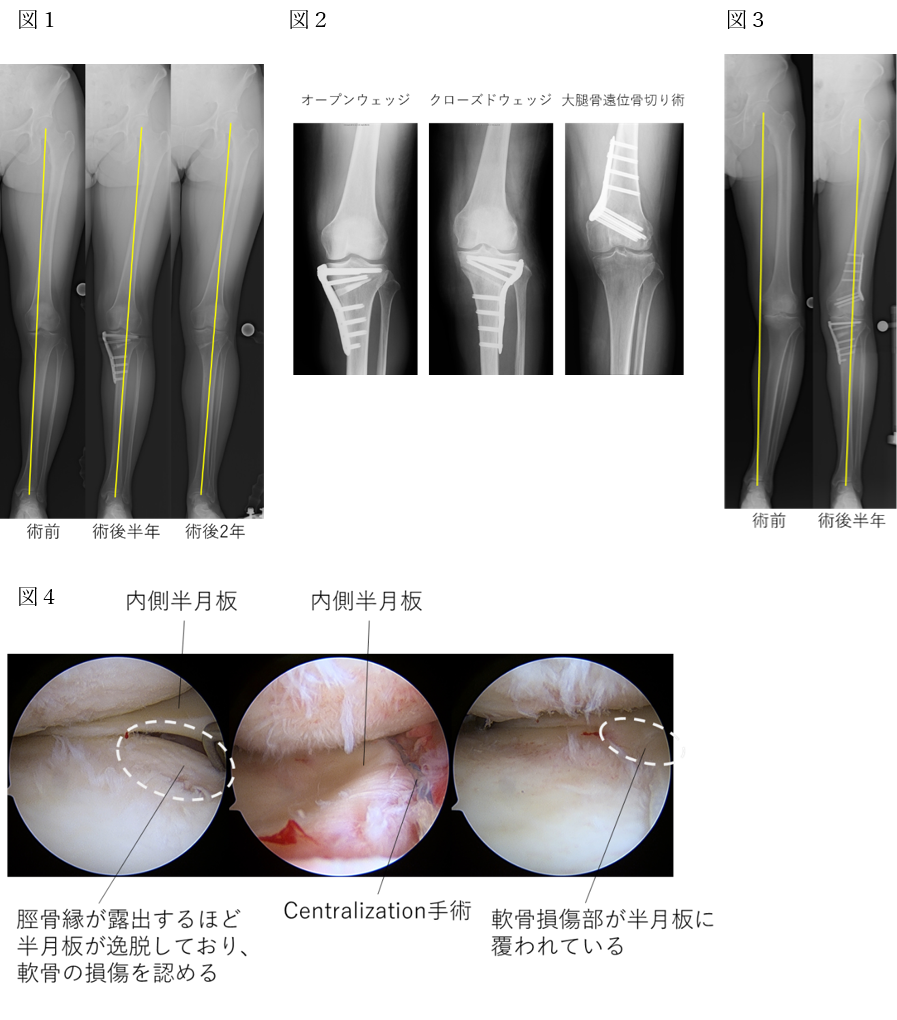

手術 開脚 膝周囲骨切り術について | 診療科・部門 | 済生会横浜市南部病院